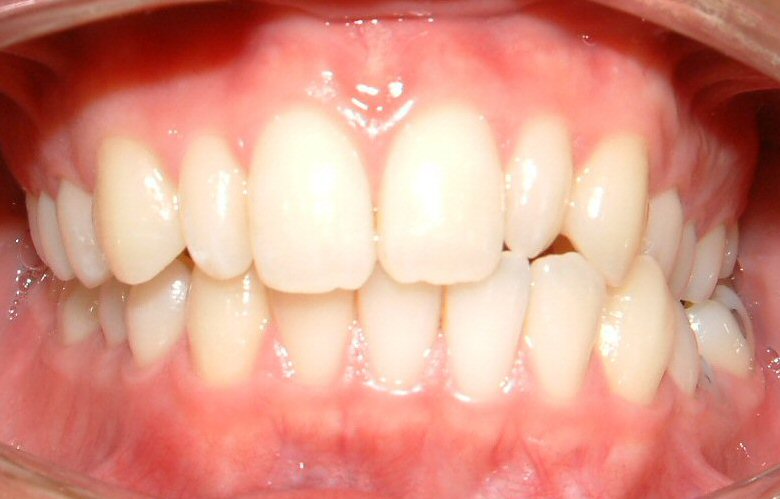

Figs. 1-7 are used with the intention of showing a case that requires a TAD. Not all orthodontic cases need TADs. The upper midline is coincident with the facial midline (not shown), but the lower midline is shifted to the patient's left about 4 mm. The lower left deciduous second molar (LLE) was ankylosed with hypo alveolar crest (radiograph not shown). The treatment plan was to extract LLE, then protract the lower left 1st molar (LL6) to close the gap of missing LLE, and to shift the lower midline to the patient's right (to match the upper midline). It would be impossible to achieve these treatment objectives with traditional technique (w/o a TAD).

Fig. 1. The lower midline is shifted to the patient's left.